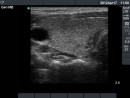

Follow-up examinations (rows from 1st to 8th):

2. Note the relation between volume, echogenicity, vascularization and hormone levels.